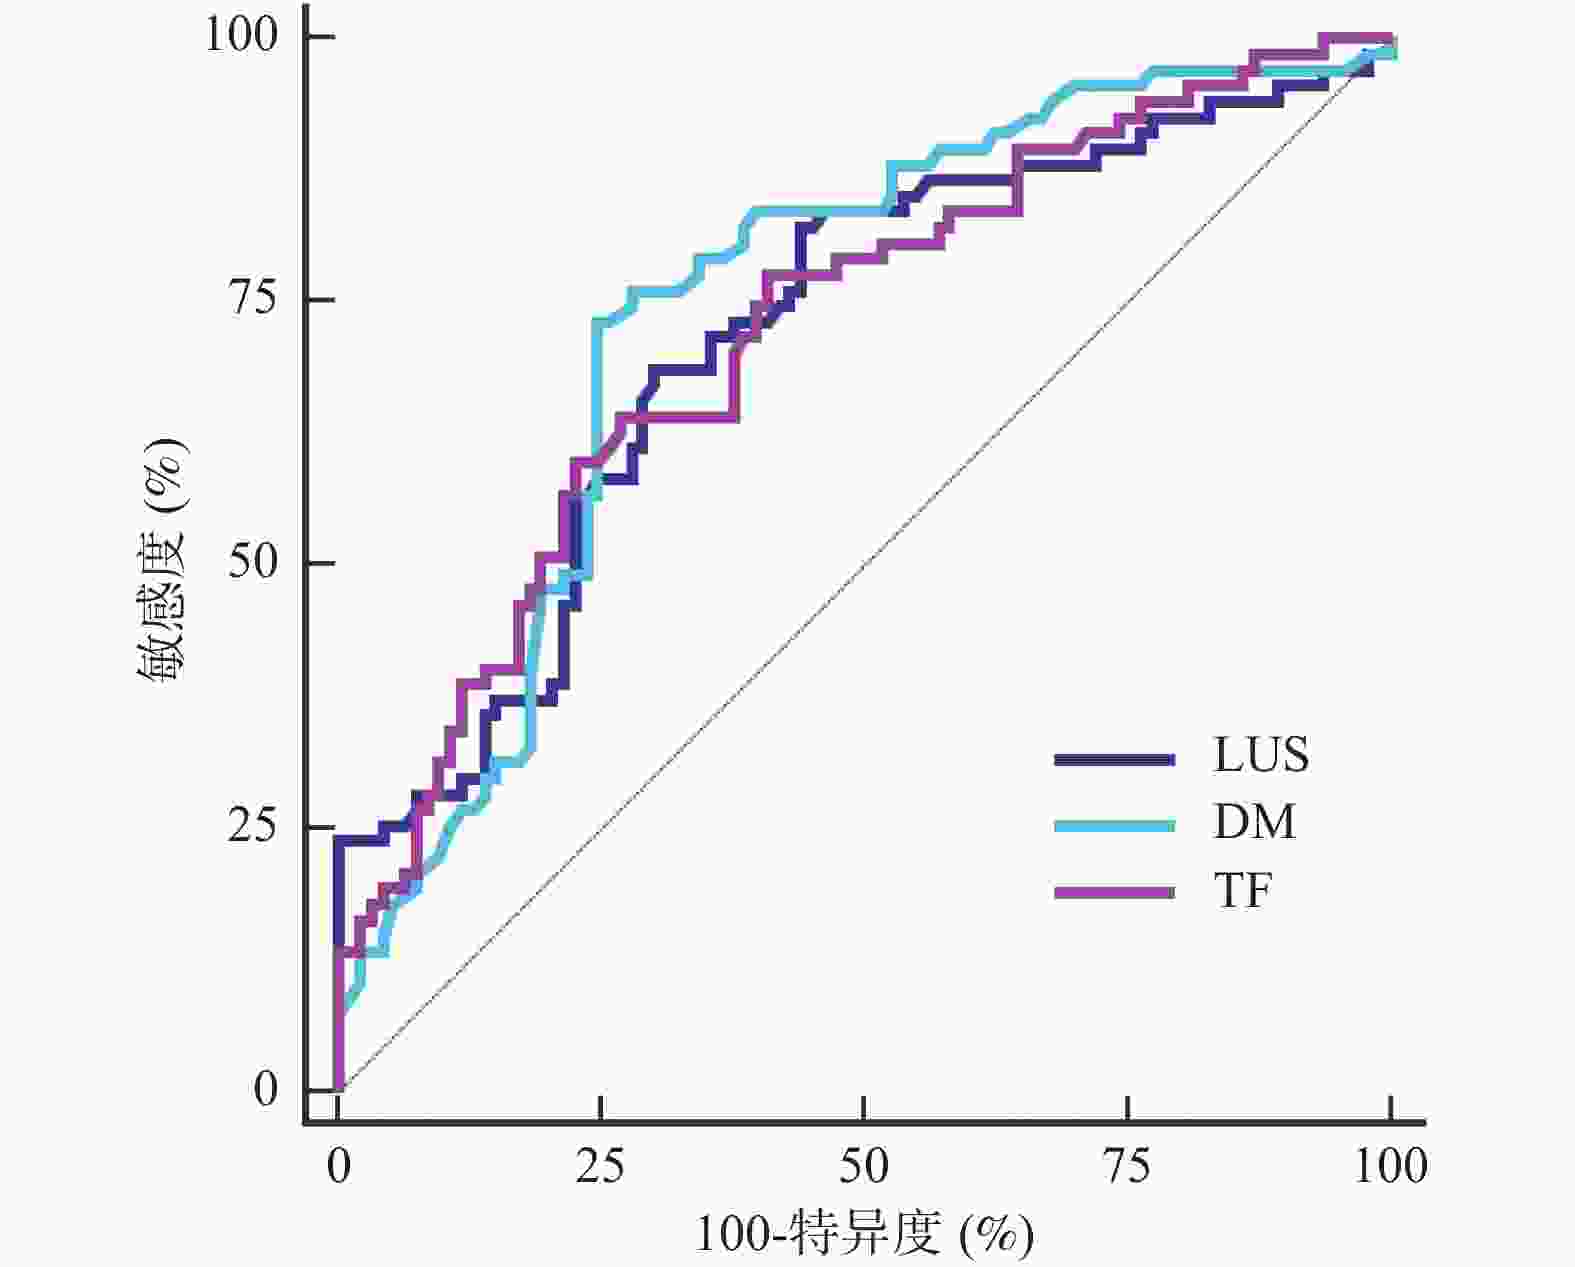

目的 探究肺部超声评分(LUS)、膈肌超声联合常规指标预测小儿重症肺炎(SP)并发急性呼吸窘迫综合征(ARDS)的价值。 方法 选取2022年8月至2023年8月昆明市儿童医院SP患儿160例,均行肺部超声、膈肌超声检查获取LUS、膈肌超声参数[膈肌移动度(DM)、膈肌厚度变化率(TF)],根据SP患儿住院期间是否并发ARDS分为ARDS组67例和非ARDS组93例,比较两组入院时一般资料、血清炎症因子水平、LUS、膈肌超声参数,分析SP患儿并发ARDS的影响因素,并分析LUS、膈肌超声参数预测SP患儿并发ARDS的价值。 结果 SP患儿住院期间ARDS发生率为41.88%(67/160);ARDS组入院时APS、APACHEⅡ评分、血清C反应蛋白(CRP)、白介素-6(IL-6)、高迁移率族蛋白B1(HMGB1)水平、LUS、DM高于非ARDS组,TF低于非ARDS组(P < 0.05);入院时APS、APACHEⅡ评分及血清CRP、IL-6、HMGB1水平、LUS、DM、TF均为SP患儿并发ARDS的影响因素(P < 0.05);LUS、DM、TF预测ARDS的曲线下面积(AUC)分别为0.718、0.742、0.720;常规预测方案(入院时APS、APACHEⅡ评分及血清CRP、IL-6、HMGB1水平联合)的AUC为0.852,新预测方案(常规预测方案基础上联合LUS、DM、TF)的AUC为0.930,新预测方案的AUC明显大于常规预测方案的AUC(P < 0.05)。 结论 LUS、膈肌超声参数DM、TF与SP患儿并发ARDS显著相关,联合常规指标可为临床预测SP患儿并发ARDS提供可靠依据。 Abstract:Objective To explore the value of lung ultrasound score (LUS) and diaphragm ultrasound combined with routine indicators in predicting the occurrence of acute respiratory distress syndrome (ARDS) in children with severe pneumonia (SP). Methods A total of 160 patients with SP were selected from Kunming Children’s Hospital from August 2022 to August 2023, all of whom underwent lung ultrasound and diaphragm ultrasound examination to obtain LUS and diaphragm ultrasound parameters [diaphragm mobility (DM), diaphragm thickness change rate (TF)]. The patients with SP were divided into ARDS group and non-ARDS group according to whether they were complicated with ARDS during hospitalization. The general data, serum inflammatory factor levels, LUS and diaphragm ultrasound parameters were compared between the two groups at admission, and the influencing factors of ARDS in children with SP were analyzed, and the value of LUS and diaphragm ultrasound parameters in predicting ARDS in children with SP was analyzed. Results The incidence of ARDS in SP patients was 41.88% (67/160). APS, APACHEⅡ scores, serum C-reactive protein (CRP), interleukin-6 (IL-6), high mobility group protein B1 (HMGB1) levels, LUS and DM in ARDS group were higher than those in non-ARDS group, TF were lower than those in non-ARDS group (P < 0.05). APS, APACHEⅡ scores, serum CRP, IL-6, HMGB1 levels, LUS, DM, TF were the influencing factors of ARDS in SP children at admission (P < 0.05). The area under the curve (AUC) of LUS, DM and TF predicted ARDS were 0.718, 0.742 and 0.720, respectively. The AUC of the conventional prediction scheme (APS, APACHEⅡ score combined with serum CRP, IL-6 and HMGB1 levels at admission) was 0.852, while that of the new prediction scheme (combined with LUS, DM and TF based on the conventional prediction scheme) was 0.930. The AUC of the new prediction scheme was significantly higher than that of the conventional prediction scheme (P < 0.05). Conclusion LUS, DM, TF, and SP parameters of the diaphragm are significantly correlated with ARDS in children with SP, and the combination of routine indicators can provide reliable evidence for clinical prediction of ARDS in children with SP. -

Table 4. Value of LUS and diaphragm ultrasound parameters in predicting ARDS in children with SP

指标 AUC 95%CI 截断值 敏感度(%) 特异度(%) LUS 0.718 0.641~0.786 19.02分 68.66 69.89 DM 0.742 0.668~0.809 1.33 cm 73.13 75.27 TF 0.720 0.644~0.788 38.50% 64.18 73.12 表 5 不同预测方案的预测SP患儿并发ARDS的价值比较